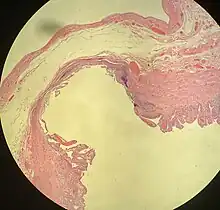

Meckel's diverticulum Large bowel (sigmoid colon) showing multiple diverticula: the diverticula appear on either side of the longitudinal muscle bundle (taenium).

Large bowel (sigmoid colon) showing multiple diverticula: the diverticula appear on either side of the longitudinal muscle bundle (taenium). Colonic diverticulum